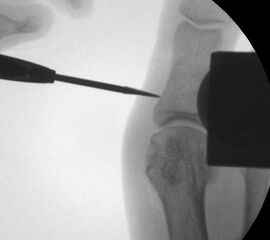

• Notwendigkeit der intraoperativen Bildvestärkerdiagnostik.

• Bildverstärker.